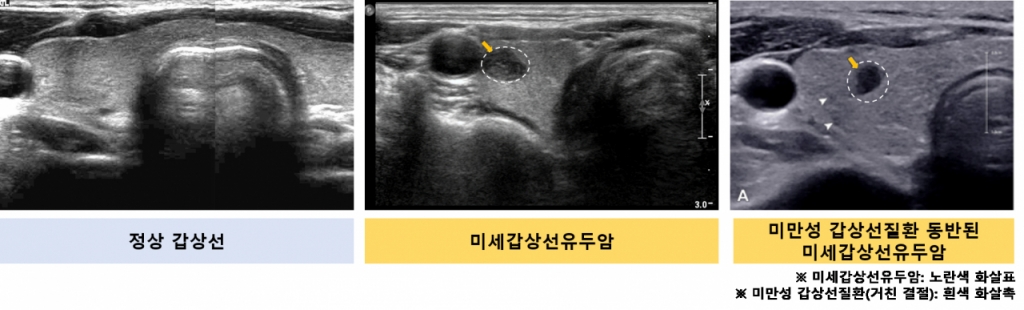

그 결과, 초음파상 갑상선 실질이 불균일하게 보이거나 혈류가 전반적으로 증가한 '미만성 갑상선 질환'과 '종양 내 혈류 증가' 2가지 초음파 소견이 종양 진행과 독립적으로 연관된 것으로 나타났다. 추적 관찰 4년 차에 두 초음파 소견이 동시에 보인 환자의 종양 진행률은 21%(48명 중 10명)로 이런 소견이 없는 환자의 종양 진행률(6%, 418명 중 25명)보다 훨씬 높았다.

추가 위험도 분석 결과 미만성 갑상선 질환 및 종양 내 혈류 증가 소견이 없는 환자와 비교해 한 가지 소견만 보인 환자는 종양 진행 위험이 2.2배, 두 가지 소견이 동시에 보인 환자는 종양 진행 위험이 3.5배 더 높은 것으로 나타났다. 특히, '종양 내 혈류 증가' 소견이 있으면 림프절 전이 위험이 약 5배 높았고 미만성 갑상선 질환 소견이 있을 땐 그렇지 않은 환자보다 종양 크기 증가 위험이 2.7배 높았다.